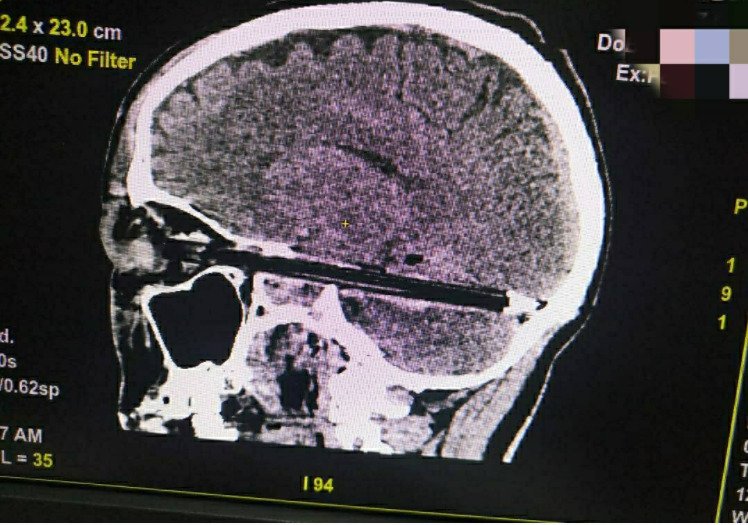

سجلت منطقة روستوف في روسيا حادث غريب لاستقرار قلم في جمجمة رجل دون سبب معروف.

وذكر الأطباء أن القلم دخل في جمجمة الرجل حتى وصلت إلى نهاية مؤخرة الجمجمة من خلال عينه.

وأضاف الأطباء أن الوقت لم يسعفهم لسؤال المريض عن سبب وجود القلم في جمجمته، لكنهم نجحوا في استخراج القلم من رأسه.